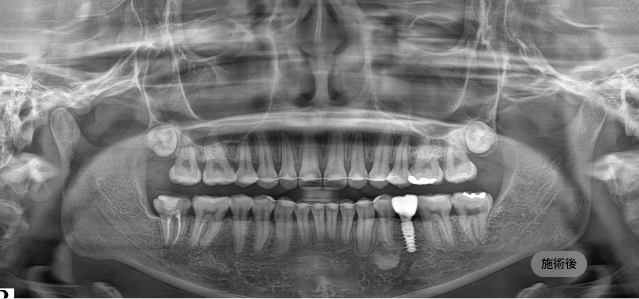

画面をドラッグして前/後を比較してみてください